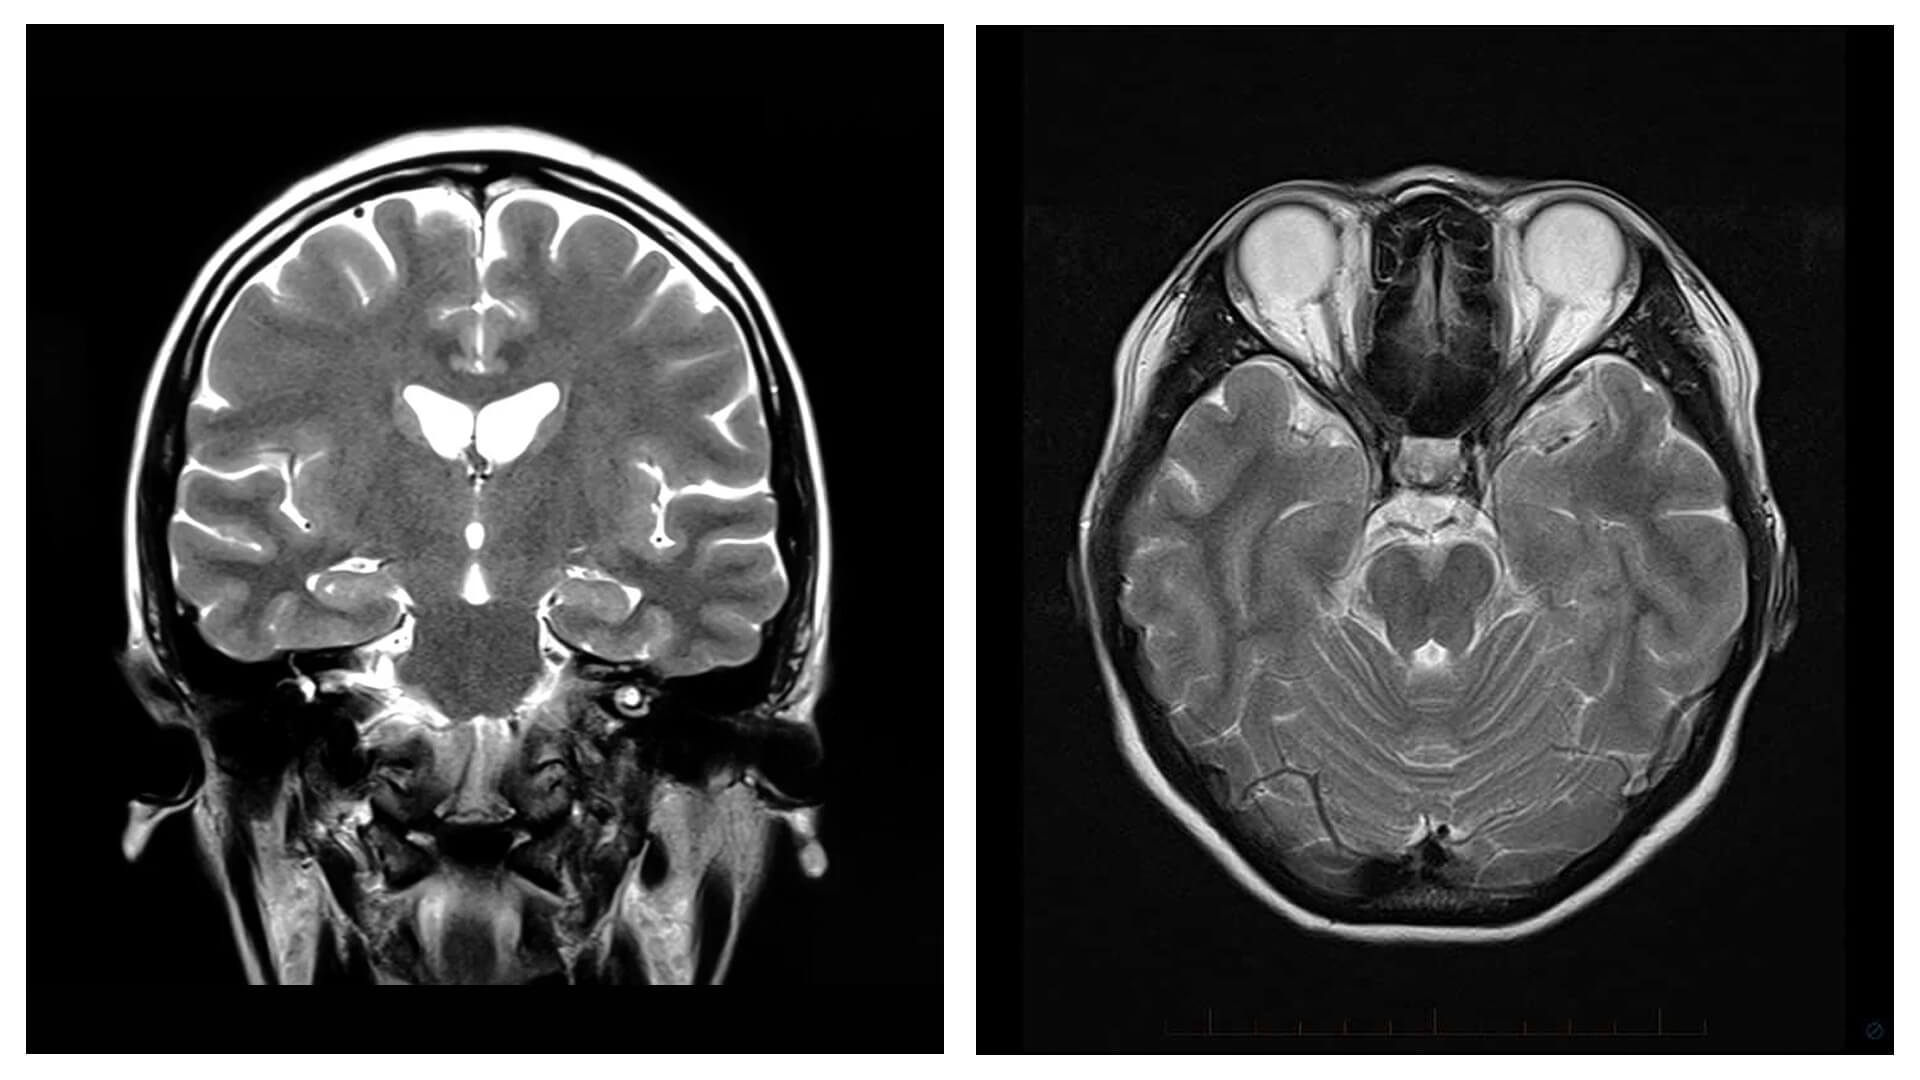

- 1000+ Radiology spotters arranged system-wise as well as miscellaneous modules with explanations and differentials wherever required

- Short/long Radiology cases with discussion

- Image gallery to view images while reading your Radiology made easy theory notes and for quick revision of important topics